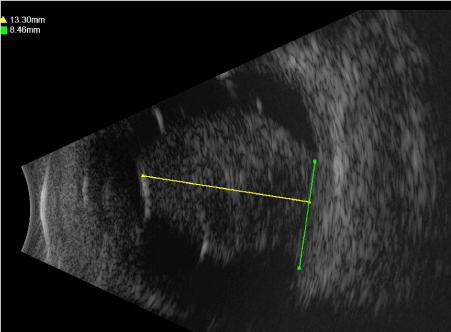

Funduscopic examination revealed a blonde fundus and a poorly pigmented solid lesion that took up the upper half of the vitreous chamber. B-scan and A-scan Standardized Echography was performed with a 20 and a 10 MHz probe and revealed a mushroom shaped lesion that broke through Bruch’s membrane measuring 15 mm in thickness, 8 mm in basal diameter (Figure 3); the lesion presented a low internal reflectivity and regular structure (Figure 4).

Figure 3. B-scan Ultrasonography. Mushroom shaped lesion that broke through Bruch’s membrane